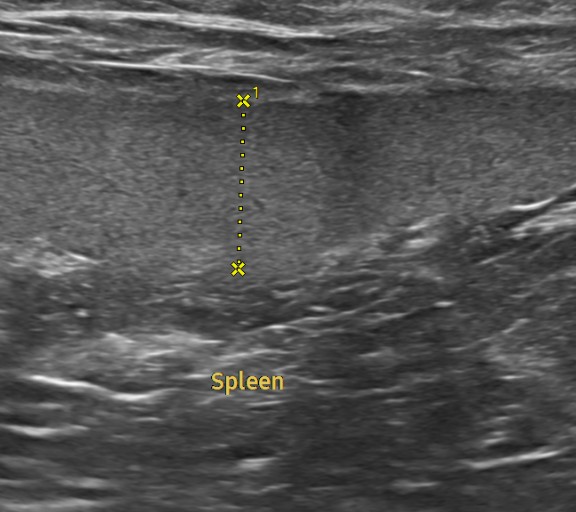

혈액검사에서는 주요 장기 수치, 염증 수치, 전해질 균형 등을 확인했고, X-ray는 흉부·복부 전반의 장기 구조를 점검했습니다. 초음파는 장기 실질 구조나 미세한 이상까지 확인할 수 있어 검진의 핵심 항목으로 포함됩니다. 치과검사는 일반적으로 마취가 동반되어, 구강전용 엑스레이 촬영을 해야 정확한 판단이 가능하지만 치과전문 병원인 만큼 육안으로 기본적인 검사는 해드리고 있습니다.